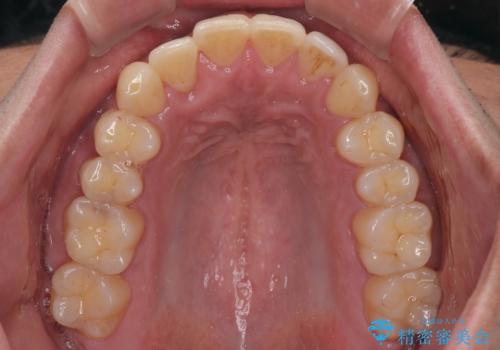

診察したところ、上下顎前歯部に軽度の叢生(ガタつき)が認められます。

目立たない装置を希望されたのでインビザライン ライトパッケージで治療を行うことになりました。